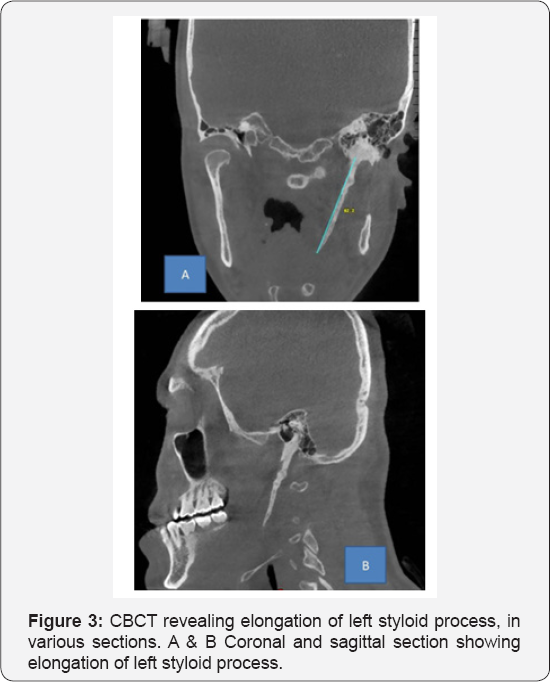

Based on the history and clinical findings, a provisional diagnosis of Myofacial Pain Dysfunction Syndrome was put forth. And Eagles syndrome was considered under differential diagnosis. Panoramic radiograph showed that the length of left styloid process to be 48mm, with Langlais type I pattern (Figure 2). Considering the elongated styloid process and suspecting eagle's syndrome, CBCT was advised. CBCT scan showed unilateral elongation of the styloid process towards the left. The actual length of the styloid process was processed using CBCT in various sections (Figure 3A-3D), and was found to be 62.2mm in comparison with the OPG, which was 48mm. Almost a difference of14mm was noticed between the two modalities. Hence showing, CBCT as the most reliable radiologic modality, to be carried out in cases where styloid process elongation is suspected. Based on the history, clinical findings and investigations, a final diagnosis of Eagles Syndrome was given and the patient was referred, for the removal of the styloid process.

The most reliable radiological investigation in recent times is the CBCT, where the exact length and extent of the styloid process can be studied. This syndrome may be treated conservatively or surgically. Conservative treatment includes transpharyngeal injection of steroids with lignocaine, nonsteroidal antiinflammatory drugs, diazepam, application of heat, traditional chinese medicines, and transpharyngeal manipulation by manually fracturing the styloid process. The most satisfactory, effective and followed treatment is surgical shortening of the styloid process, either through an intraoral or external approach. Advantage of an external approach is the proper exposure of the styloid process and the adjacent structures, and this advantage outweighs all the other considerations and also facilitates the resection of a partially ossified stylohyoid ligament. Transoral resection prevents outside scars, but carries the risk of deep cervical infection with possible injury to the neurovascular bundles [10].